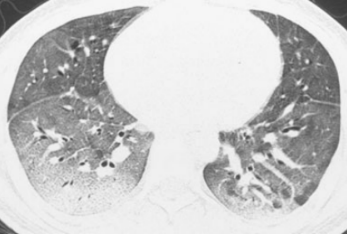

图4 45岁男性急性髓系白血病患者

注:在allo-HSCT术后6个月后出现呼吸困难。A. 胸部CT显示支气管周围磨玻璃样改变;B. 1个月的随访CT显示疾病进展,磨玻璃样改变的范围增加、新进展的网格影及铺路石影、明显牵拉性支气管扩张[22]。